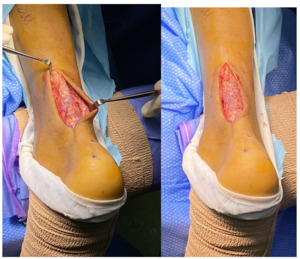

A BioBrace 23x30mm implant was cut in half length-wise to create two strips measuring approximately 12mm x 30mm each and in order to better fit the tendon defect. These strips were placed end-to-end within the defect (Figure 3) and sutured in place using a Krackow-type stitch starting from the proximal end, progressing to the distal end, and then back up to the proximal part of the defect (Figure 4). The remaining Achilles tendon tissue was enclosed around the BioBrace to create a tubular type configuration. The repair was completed using suture tape for additional reinforcement. Whether or not a larger gap could be treated with this technique is beyond the scope of this report and could be further assessed in a future study.